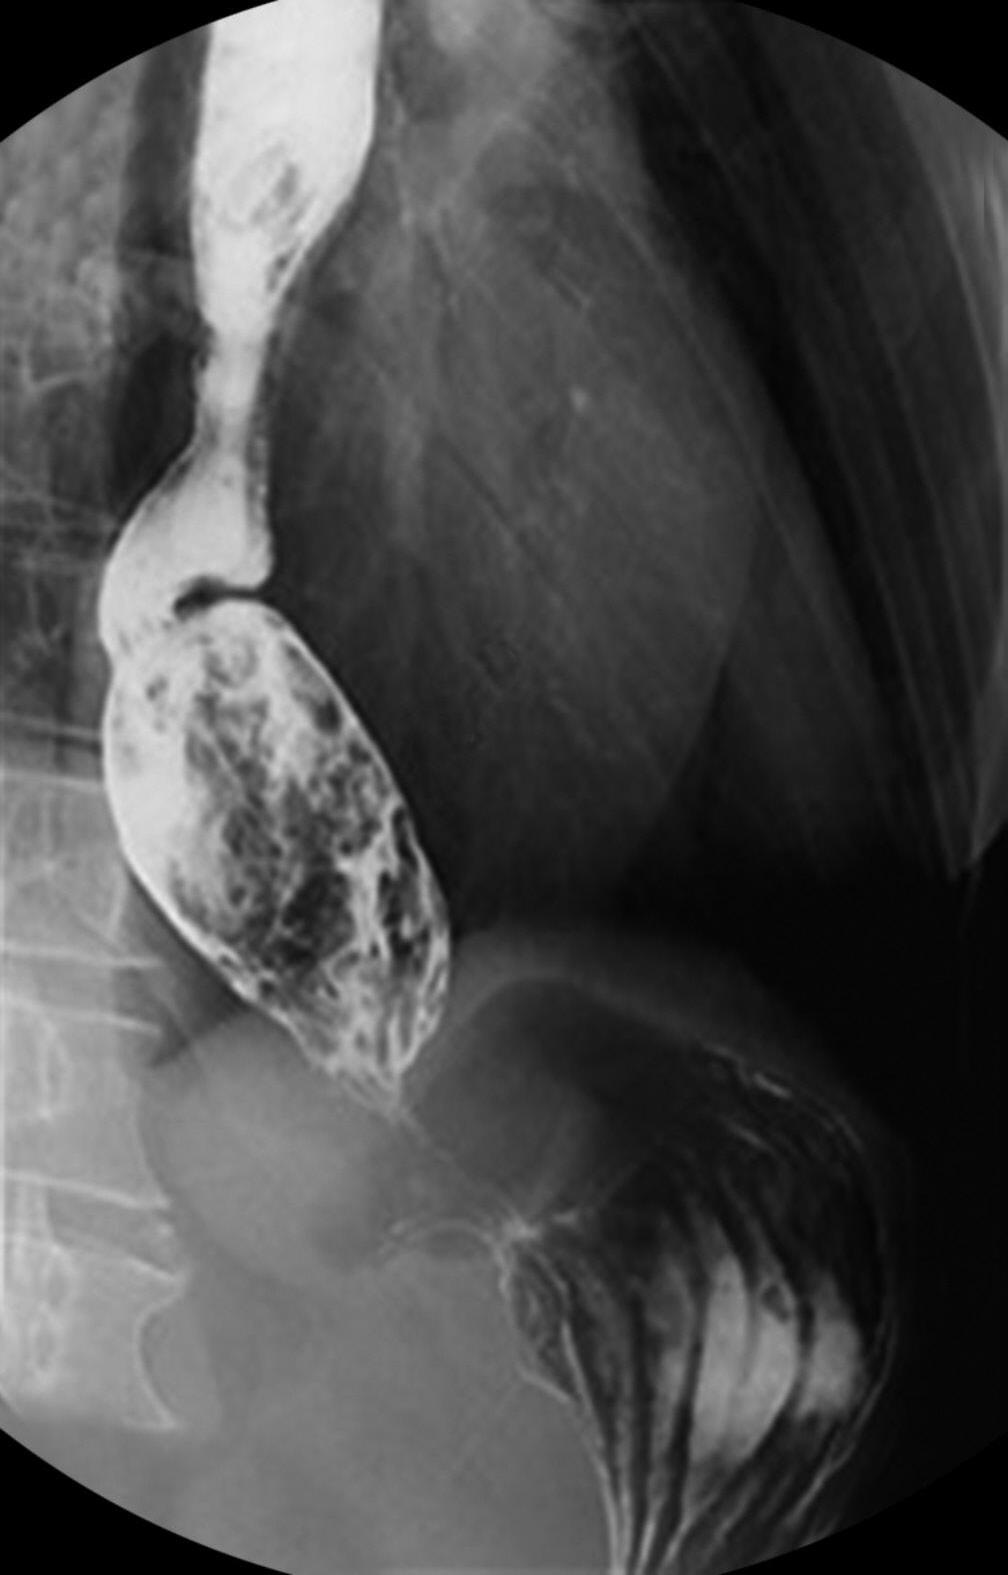

Figura 7.1 (A a C) Radiografia contrastada de esôfago demonstrando . Junção esofagogástrica sem relaxamento e afilada com aspecto de bico de pássaro (seta) (A) Esôfago dilatado com estase do contraste formando nível hidroaéreo (seta) (B) . Esôfago “sigmoidizado” (dilatado e tortuoso) com resíduos alimentares (seta demonstrando áreas escuras compatíveis com resíduos alimentares em meio ao contraste branco) (C)

Fonte: imagens dos autores